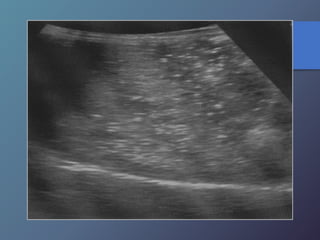

Cirrosis Hepática

Proceso difuso hepático caracterizado

por fibrosis y la conversión de la

arquitectura normal del hígado en

nódulos estructuralmente anormales.

• Redistribución de volumen. Índice

caudado/lob. Der. 0.65.

• Ecoestructura grosera.

• Superficie nodular.

• Nódulos de regeneración.

• Nódulos displásicos.

• Hipertensión portal: Ascitis, esple-

nomegalia, varices.

Características Ecográficas